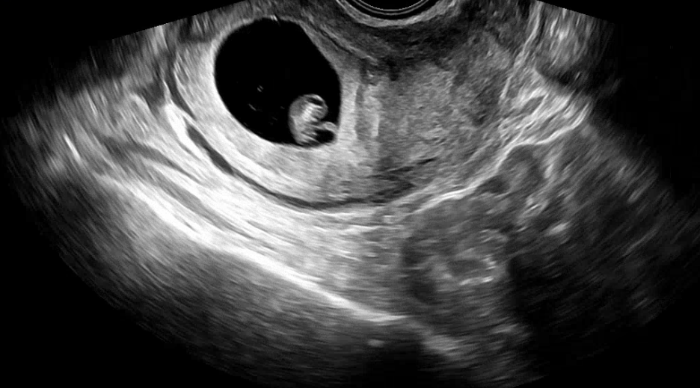

초기라 질초음파로 아기집을 확인했어요. (10주 이후부터 배초음파로 볼 수 있습니다)

과연 일주일 동안 아기집이 잘 생겼을지 걱정반 기대반😌

다행히 자리도 잘 잡았고 크기도 괜찮다고 하셨어요. 작은 난황도 보였네요.